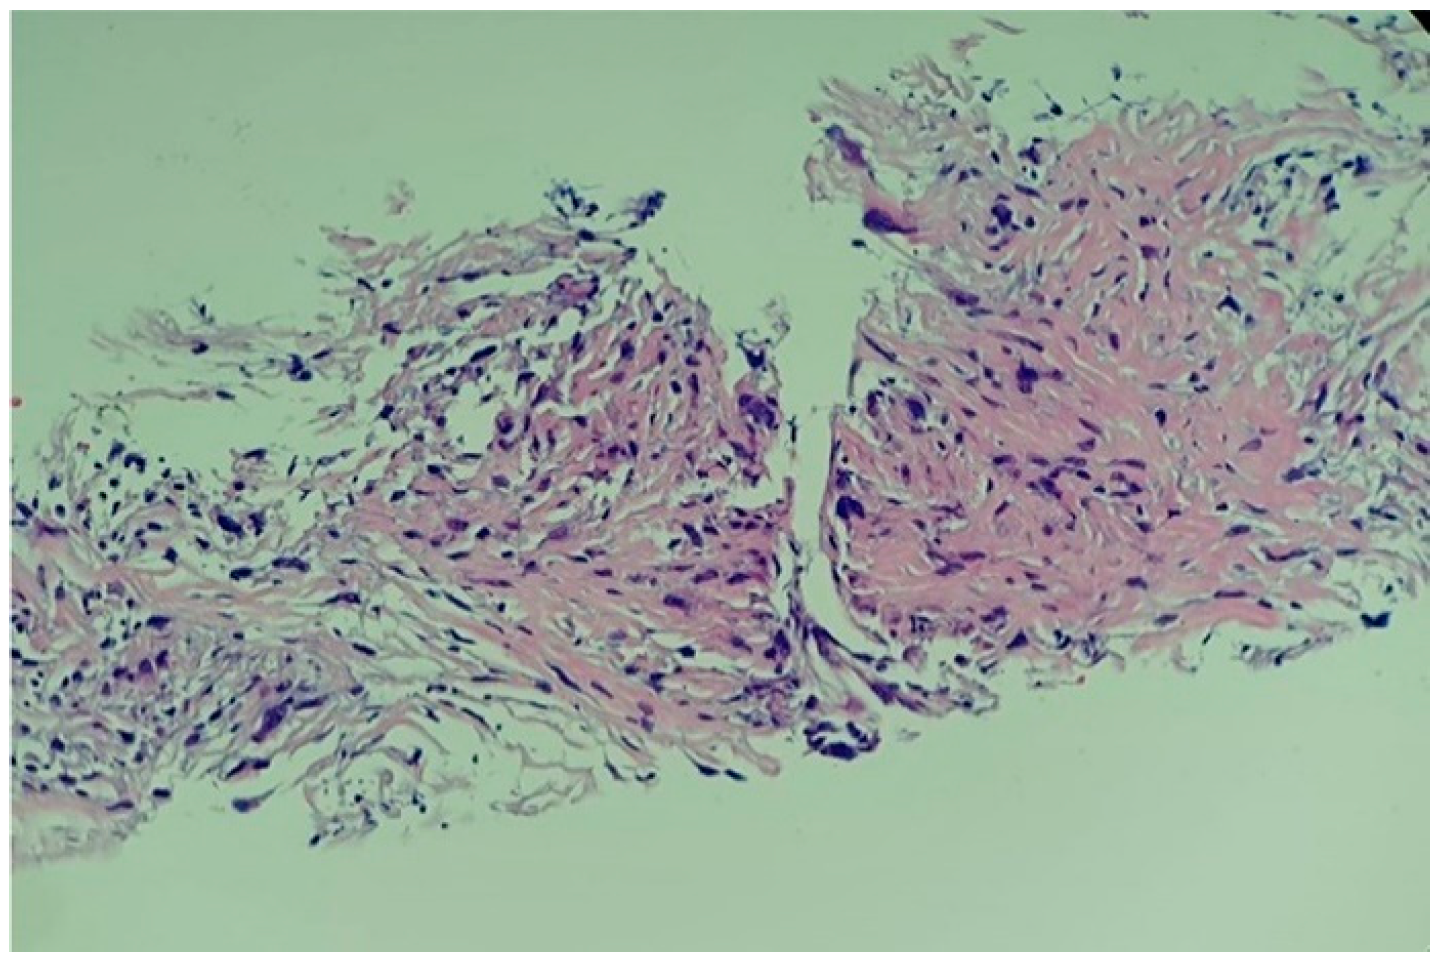

A complex multidisciplinary team supervised the biopsy that was performed in the operating room. Transthoracic ultrasonography using a convex probe identified the apical tumour, the absence of hypo-echogenic left ventricle motility in contrast with the remaining myocardial wall, and the infiltration of the adjacent pericardium. The biopsy was performed via the left inferior parasternal route by using an ultrasound-guided 10 cm 20G coaxial biopsy needle inserted percutaneously. Three tumour fragments of 1 by 2 cm were obtained. No incidents were recorded during or after the procedure. Histological reports confirmed the presence of a high-grade primary intimal cardiac sarcoma with areas of myxoid differentiation and epithelioid-appearing cells (Figure 9).

Immunohistochemistry analysis revealed a positive reaction for MDM2 and a Ki67 proliferation marker of 20% to 80% in tumour cells (Figure 10). The samples were found negative with regard to myogenin, CD31, CD34, D2-40, and desmin. Despite the prompt individualized diagnosis, the patient died three weeks later.

4.3. Core Role of MDM2 Assays as First-Line Analysis and Re-Do Perspective

In this case, histological examination revealed an intimal sarcoma with areas of myxoid differentiation and epithelioid-appearing cells. The MDM2 (immunohistochemistry-based) tumour marker is considered to be useful for high-grade intimal sarcomas nowadays. MDM2 (an oncogene that is responsible for blocking the activity of p53) is defined by nuclear overexpression and amplification of the 12q12–15 area, which contains CDK4 (cyclin-dependent kinase inhibitor 2A) and MDM2 [17,18], the MDM2 amplification supporting the diagnosis of intimal sarcoma [17]. Additionally, the intimal sarcoma with a positive stain for MDM2 has been shown by some studies to be associated with a poor prognosis, with a median survival of three to twelve months [17,18]. In contrast, Cho et al. [25] showed that MDM2-positive show a better outcome than MDM2-negative tumours [25]. One more clue of the expected dramatic outcome is the increased value of the Ki67 proliferation marker at immunohistochemistry analysis, as seen in the present case (20% to 80% depending on tumour area), which is similar to other reports of different sarcomas such as osteosarcomas or leiomyosarcomas [17,18,79,80].